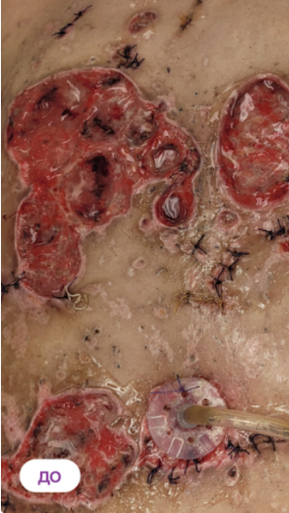

Левая молочная железа: некроз ореолы и отек; Правая молочная железа: линейные нормотрофтчекие рубцы, выраженный отек, напряжение ткани,болезненность, гематомы и блеск кожи в области операции

Проблема появилась после проведенной в октябре 2023 года пластической операции с целью замены ранее (в 2010 году) установленных имплантатов. Послеоперационный период (со слов пациентки) протекал с особенностями: на 3-4 день на перевязке обратила внимание, что область ареолы левой молочной железы имеет не характерный черный цвет, уплотнение и отсутствие розовой и живой кожи. Лечение по месту проведения операции не помогло.

Назначено: ФДТ REVIXAN с ФС Derma PRO - 4 процедуры дополнительно была назначена системная терапия и домашний уход

Параметры изменяются в зависимости от процедуры

Дата публикации: 22.08.2025 14:37:57